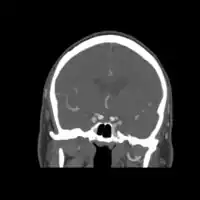

-

Carotid artery dissection -

Dissection of the carotid artery on ultrasound